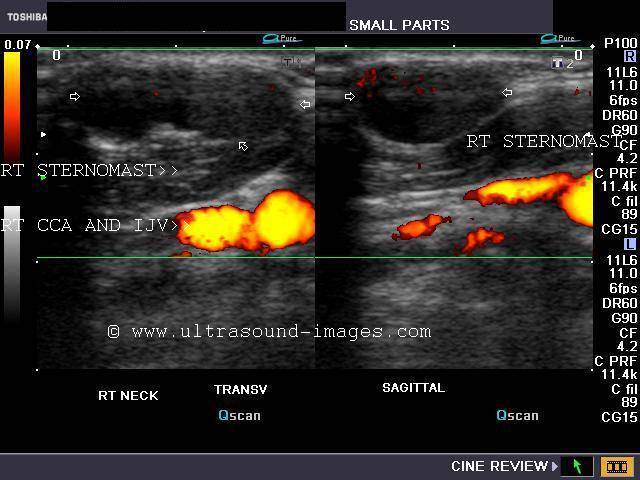

Sonography of the thyroid in this 1 yr. old female child revealed congenital absence of the entire thyroid. Note the empty fossae where the right and left lobes would normally lie. The carotid artery and jugular vein of both sides are seen in the color doppler images. These ultrasound and color doppler images suggest congenital agenesis of the thyroid.